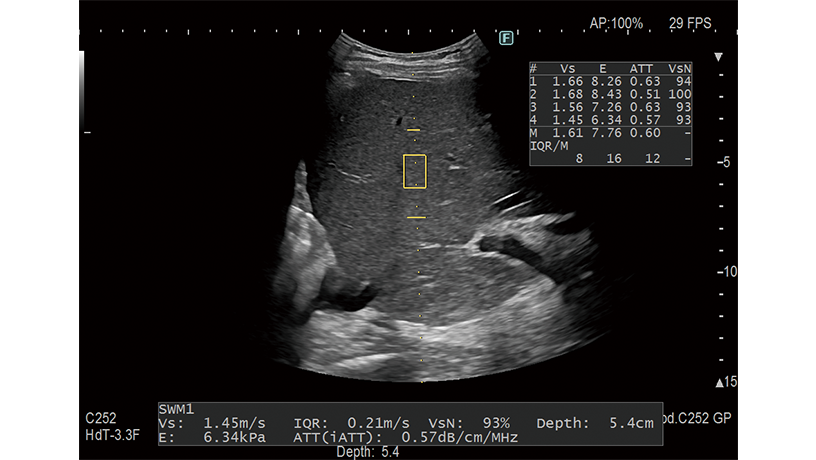

It is possible to evaluate tissue stiffness by generating shear waves and measuring Vs, its propagation velocity in the tissue. Combi-Elasto, which integrated RTE and SWM, is expected to be used for cases which are difficult to diagnose through only using SWM.

A function to measure the attenuation coefficient generated in the process of ultrasound propagation of tissue. The degree of steatosis can be estimated from the size of the coefficient. Its measurement is conducted simultaneously with SWM, and it can be conducted as an extension of B mode examination.